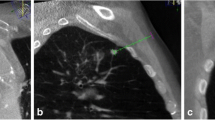

As the second step, the needle path was planned on the same workstation using commercially available software (Syngo iGuide, Siemens Healthcare). Figures 1, 2, 3 and 4 demonstrated this procedure for a 0.5-cm in diameter pulmonary lesion, and Figs. 5, 6, 7, and 8 demonstrated this procedure for a 2.0-cm in diameter pulmonary lesion. The reconstructed 3D volume was first loaded. In the orthogonal multiplanar images, the skin entry point and target lesion positions were manually selected and marked by a cross and a circle, respectively. A virtual path was then generated with its angulations and length calculated and displayed. All three multiplanar images were automatically aligned to the defined path to provide in-plane views (Figs. 2, 6). This procedure could be iteratively performed, modified, and reviewed until a satisfying path was obtained.

CBCT orthogonal multiplanar images with graphics showing planned needle path (yellow line) into target lesion (red circle) (a–c). The cross indicated the skin entry site and the circle indicated the target lesion site. The needle position relative to the anatomical structures was displayed in 3D using volume rendering technique (d)

In order to use the planned path to align the needle in actual 3D space, the virtual path was then projected and superimposed onto the live fluoroscopic images and displayed on a dedicated live monitor (Figs. 3b, c, 7a, b). The software automatically calculated the C-arm angulations, table motion, image zoom, and then controlled the C-arm moving to reach the desired position. First, the C-arm rotated to the Bull’s Eye View, where the C-arm was angulated in the way that the cross and the circle displayed on the live monitor completely matched and the central X-ray beam was aligned with the planned path (Figs. 3b, 7b). The laser navigation system on the Flat-panel can quickly locate the needle point on skin, Thus the skin entry point could be determined (Fig. 3a). The needle orientation was adjusted until both the tip and hub of the needle in the fluoroscopic image were superimposed and located at the centre of the circle and the cross. Second, after the skin entry point and needle orientation were determined, the needle was advanced under fluoroscopy until the planned target lesion position was reached. The C-arm was rotated back and forth to two different angles subsequently to monitor the needle progression. These two angles provided lateral views (progression view) of the planned needle path and helped to ensure that the needle was advanced along it (Figs. 3c, 7b). Third, a 3D scan was acquired to confirm the final position of the needle (Figs. 4, 8).